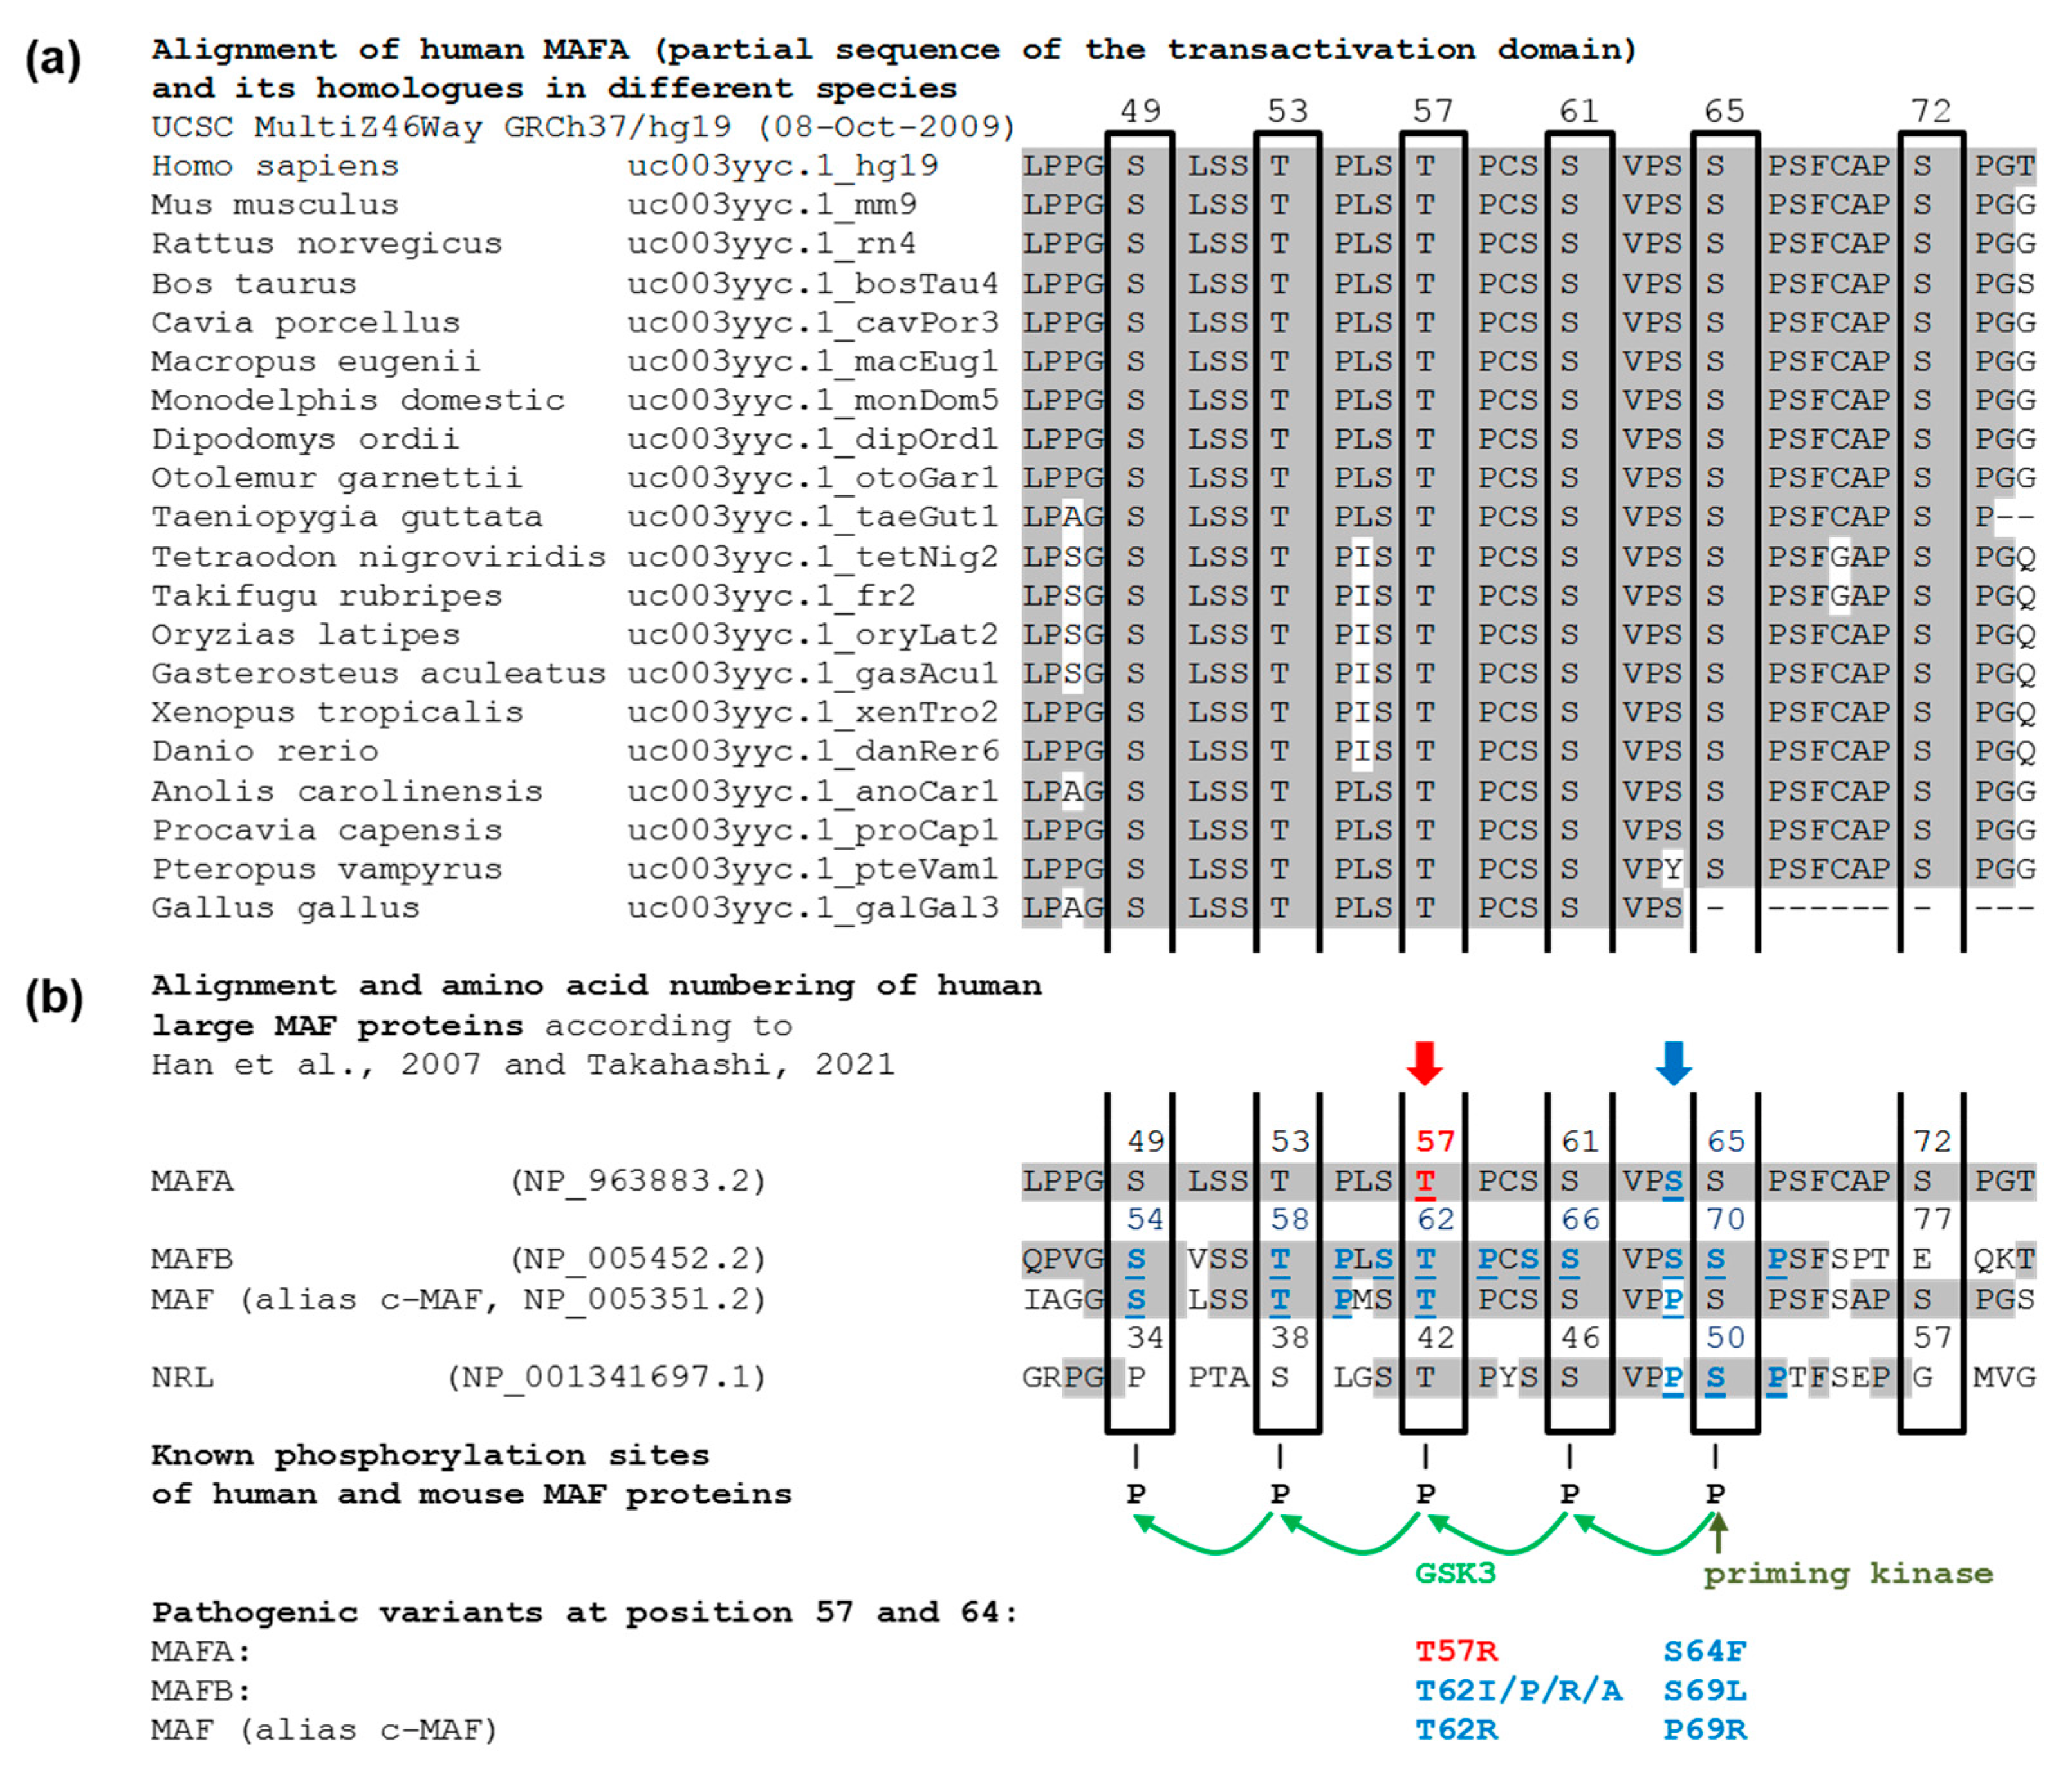

3.2. Molecular Genetic Testing

3.2.1. Molecular Genetic Testing of the Two Patients and Classification of the Detected Variants According to the ACMG Criteria

4. Discussion